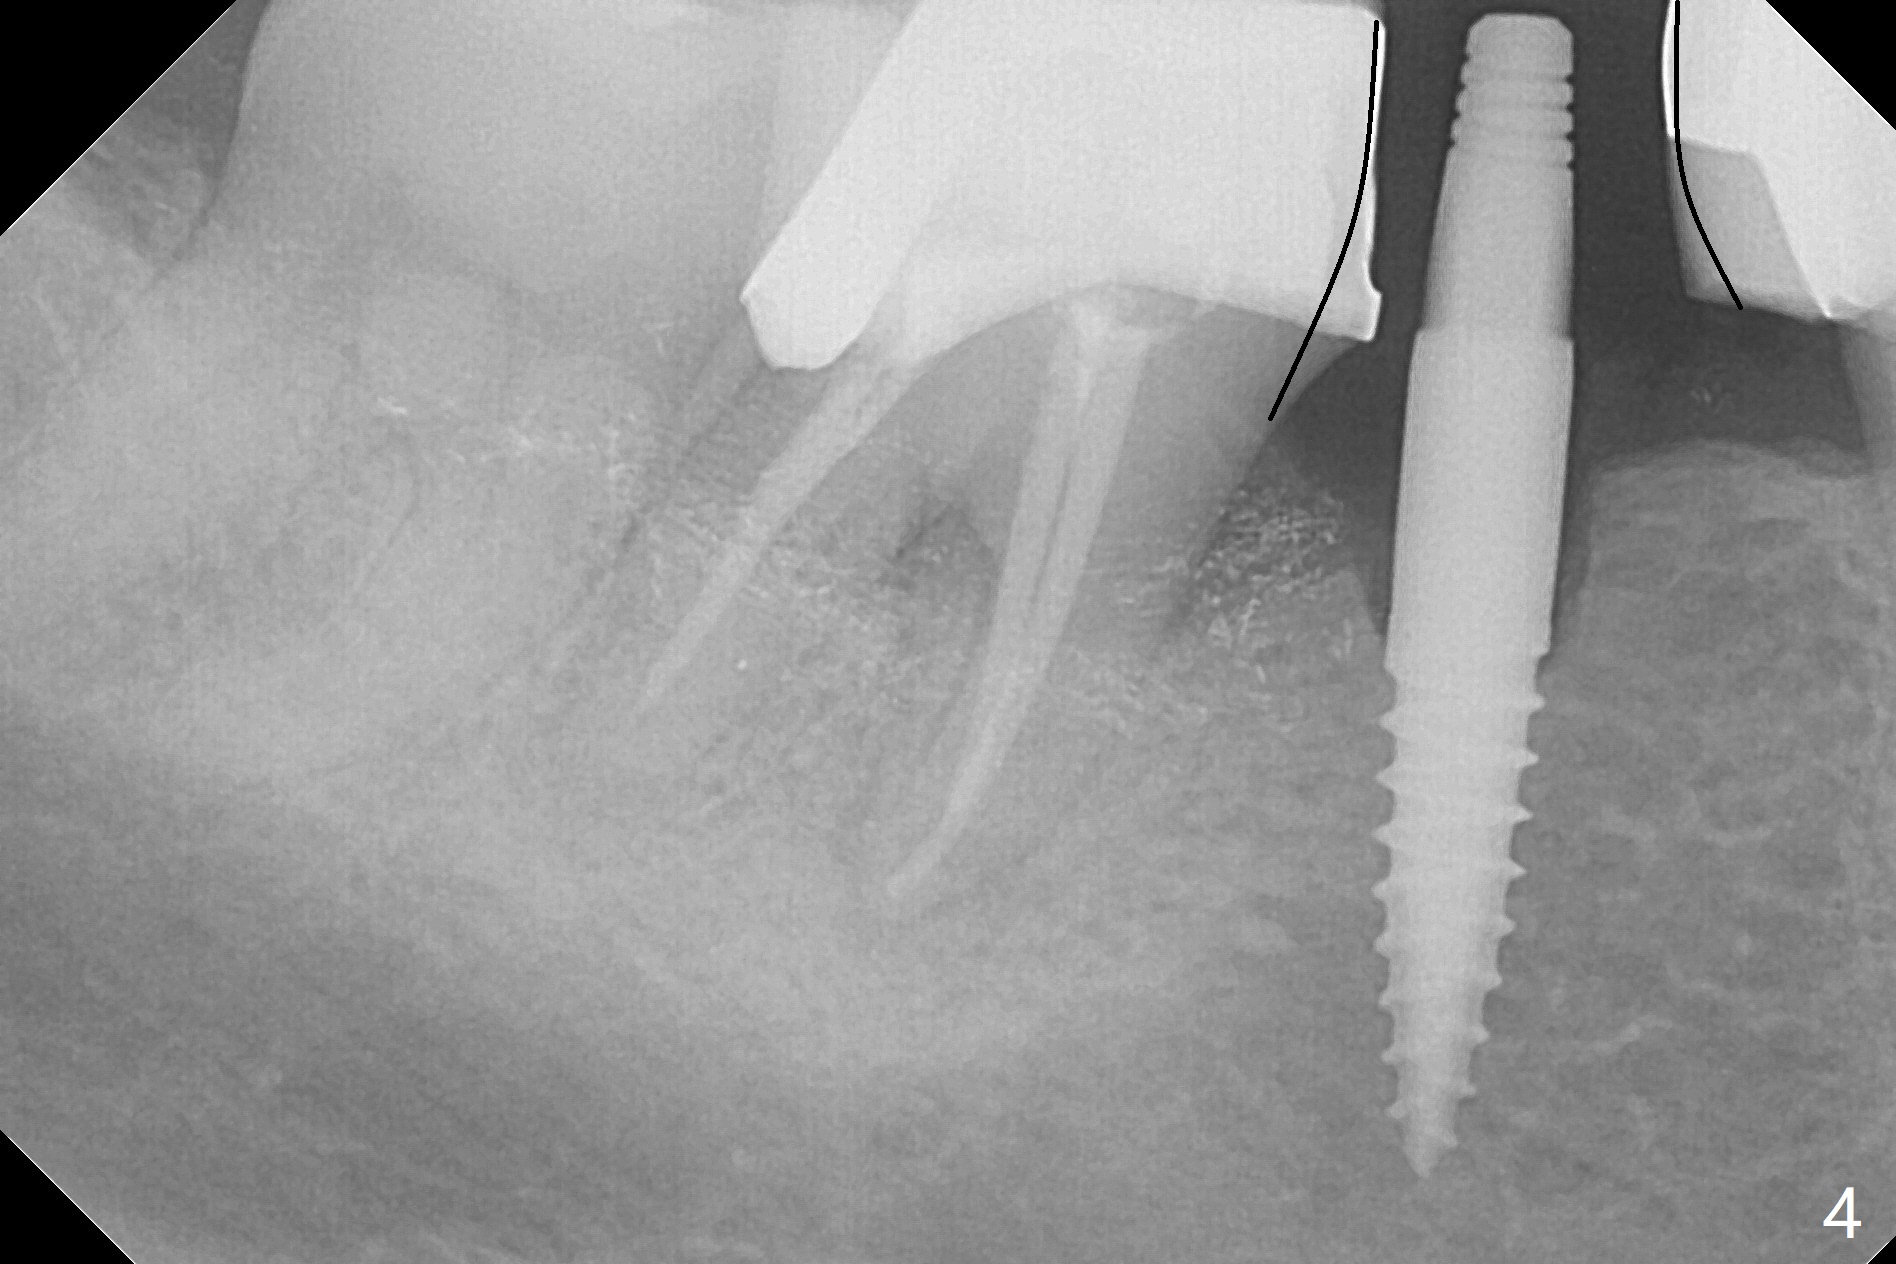

There is a space underneath the pontic at #30 (Fig.1 *), the basis for food impaction. After sectioning between the pontic and the posterior retainer, the pontic is removed from the anterior retainer with an attachment (Fig.2 *). The initial depth of osteotomy is 10 mm following ridge top reduction (Fig.3). A 3x10(4) mm 1-piece implant is placed with >50 Ncm; to reduce possibility of crown dislodgement from the implant, the retainers will be kept with modification of the proximal surfaces as shown by curved lines in Fig.4. Periodontal dressing is applied after suturing. There is no postop paresthesia. The periodontal dressing remains in place 2 weeks postop because of engagement into the attachment slot and undercuts (Fig.5). The patient returns 3 months postop; after minor contour adjustment (Fig.6 red curved line), impression is taken. The permanent crown is temporarily cemented (3.5 months postop) in case of food impaction due to the distal overhang of the tooth #29 (Fig.7). In fact the patient returns 4.5 months post cementation with right TMD (muscle relaxant prescribed) and food impaction, although there is no bone resorption (Fig.8,9). It appears that the crown at #29 needs to be redone, while porcelain will be added to the mesial surface of the one at #30 (Fig.10 red lines). In fact the crown at #30 is redone because of loose proximal contact with #31; there is no bone resorption 13 months post cementation (Fig.11). Bone resorption remains unnoticeable 28 months post cementation (Fig.12,13).